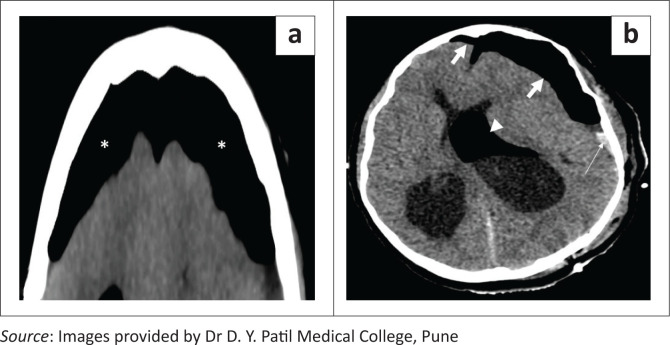

FIGURE 14.

Axial soft tissue window CT image (a) shows tension pneumocephalus in both frontal regions (asterisks) causing mass effect on the underlying brain parenchyma with a heaped-up appearance of the anterior tips of the bilateral frontal lobes (Mount Fuji sign). Axial soft tissue window CT image (b) in a different patient shows asymmetric tension pneumocephalus (thick white arrows) in both frontal regions (left > right), causing mass effect on the underlying brain parenchyma and subfalcine herniation towards right side. There is an associated subdural hemorrhagic collection (thin white arrow) present on the left side and postoperative air in the left lateral ventricle (arrowhead).

The diagnosis of tension pneumocephalus is made on CT in the presence of subdural air with the ‘peaking’ sign and the ‘Mount Fuji’ sign (Figure 14a). ‘Peaking’ sign refers to mass effect on the frontal lobes because of the presence of subdural air and the ‘Mount Fuji’ sign refers to separation of the frontal lobes from the falx.18